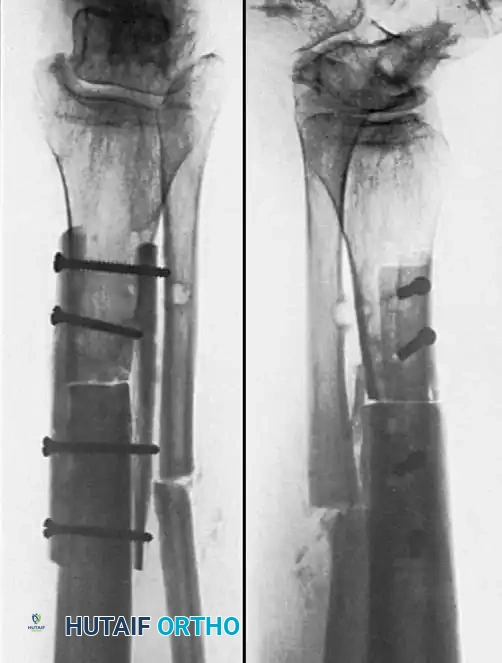

Associated Surgical & Radiographic Imaging